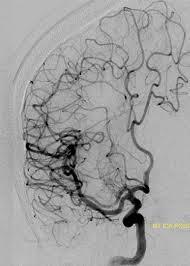

61 year old man

Presents with right arm and leg numbness and weakness and slurred speech. Symptoms lasted about 20 minutes and resolved

PMHx: type I diabetes, hypertension, and hyperlipidemia

Exam on presentation is normal

Had embolism from carotid artery let loose

microembolism from severe atherosclerotic carotid stenosis

***

Why isn’t cardioembolism as likely? – Doesn’t as easily get better (fewer TIA’s more

large strokes)

– With a shower of emboli, would expect to see in ALL territories (left and right, anterior and posterior)